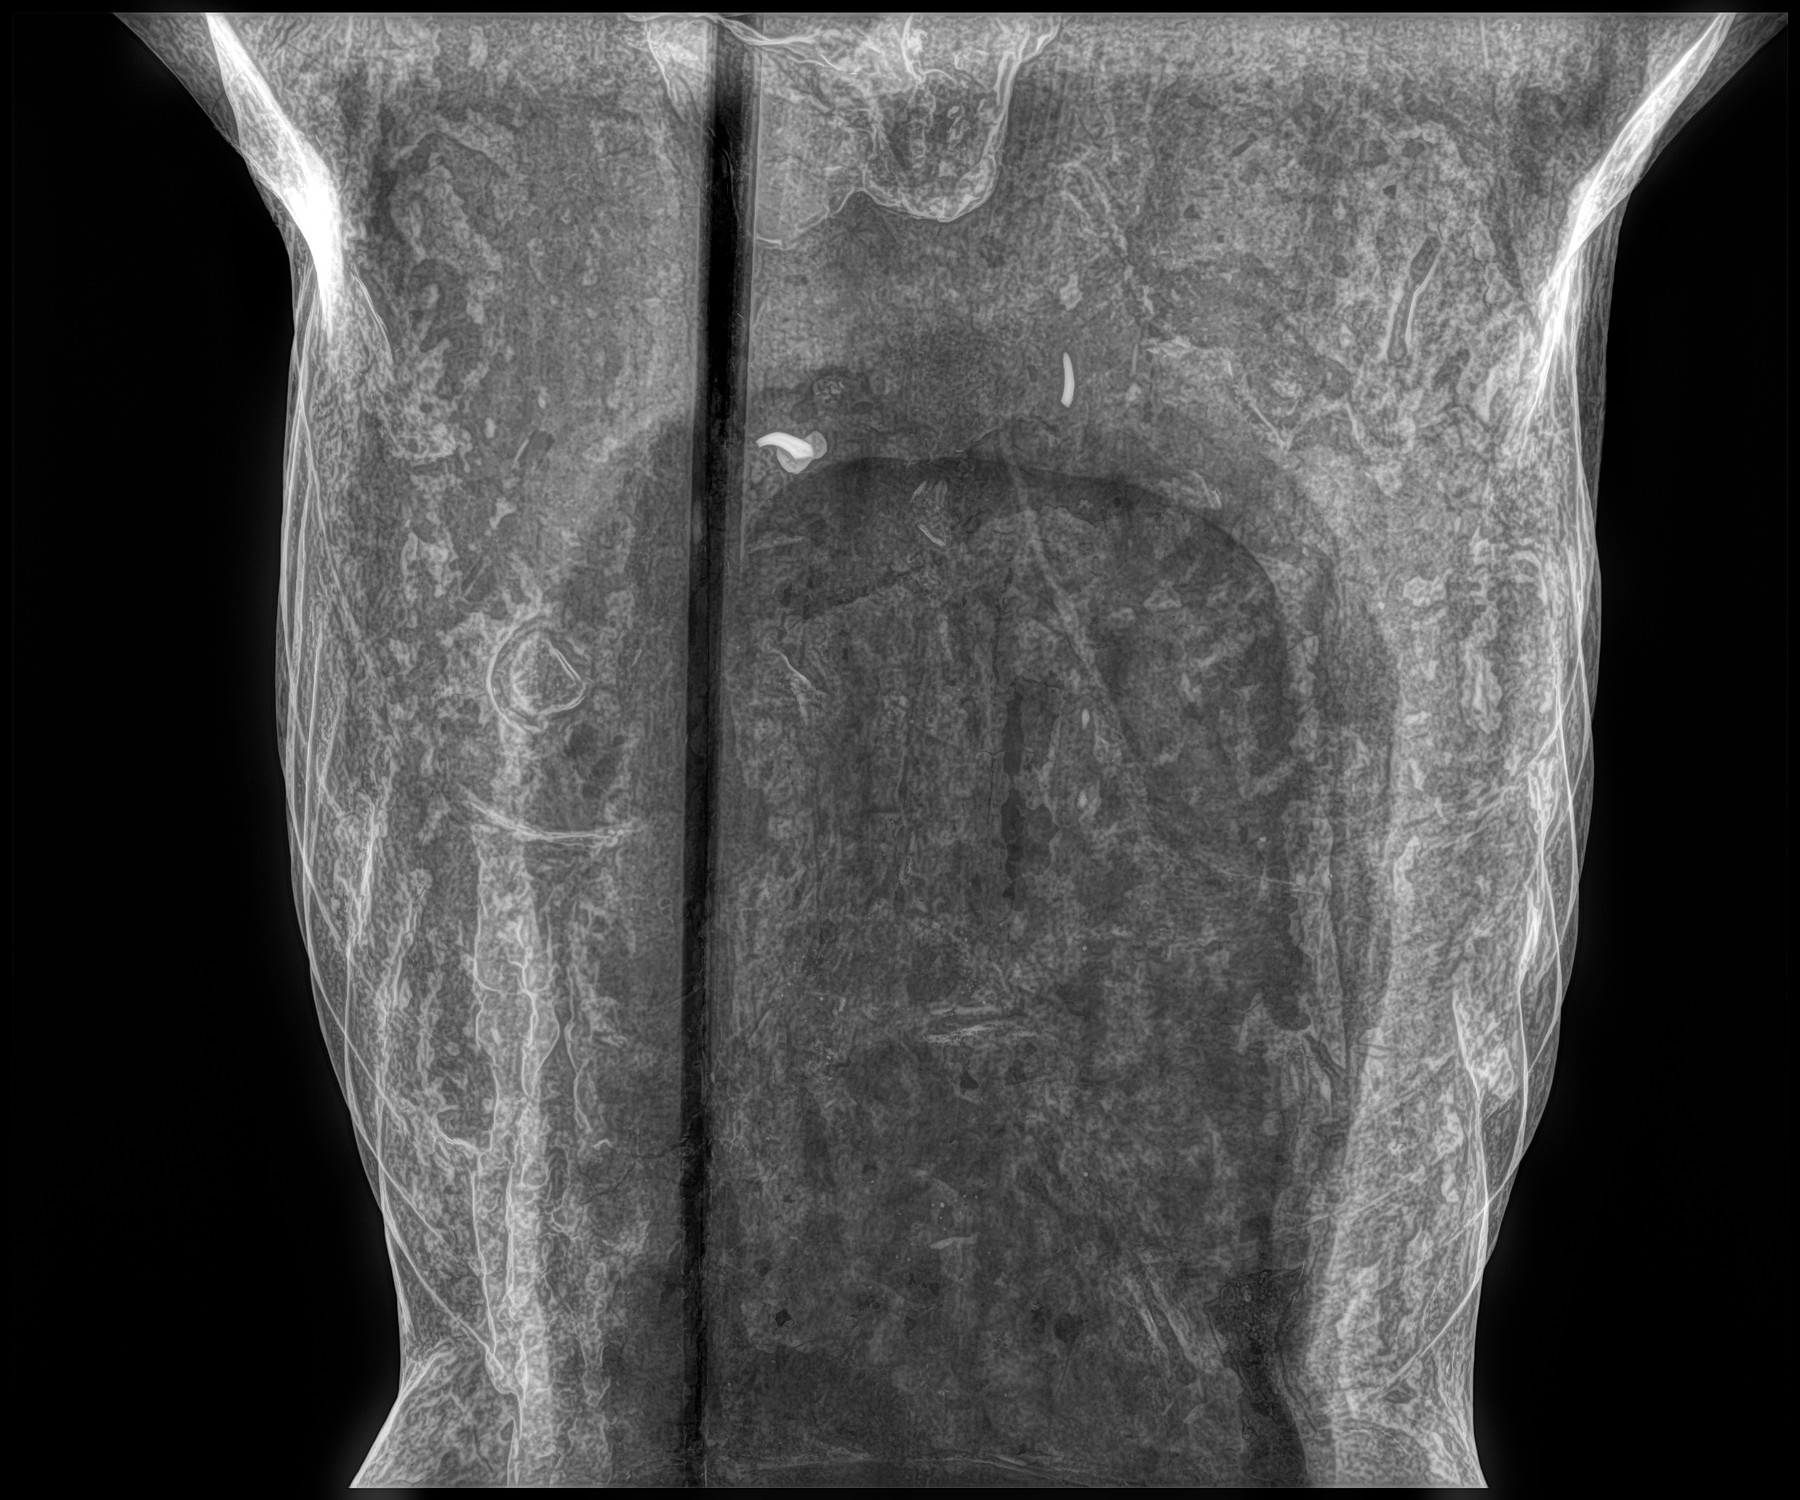

Cambios Térmicos en las Extremidades de Caballos,

Asociados a Golpes y su Evaluación por Termografía.

Los caballos de salto, en competencia, pueden derribar obstáculos y lastimarse. Si se golpean, no siempre claudican. Considerando al calor como un signo de inflamación, se evaluaron los cambios térmicos de 6 áreas de las extremidades torácicas y pelvianas de 23 caballos de salto en nivel de competencia de 1.05 a 1.60 m de altura, por medio de termografía durante 4 días de competencia (N=2208 áreas).